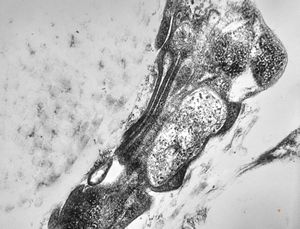

F, 8y. | metachromatic leukodystrophy … n. suralis